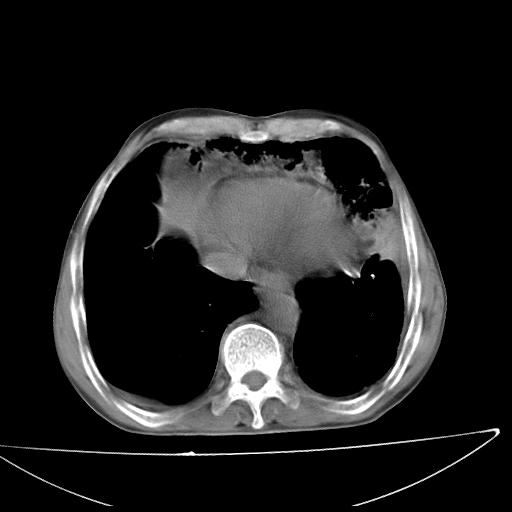

男  70岁,发烧咳嗽4天。盗汗,消瘦。无痰中带血丝,以前有肺tb病史,ct见,双肺tb,左侧胸廓塌陷,左胸膜肥厚粘连。纵隔移位,右侧胸腔积液,大家说说那个心影前左肺舌叶除了肺大炮还有炎症还是干酪性肺炎?有占位吗?我看纵隔淋巴结也大。

1)两肺继发性肺结核并左肺上叶肺不张,支气管扩张。2)双侧胸膜炎(胸膜增厚+少量胸腔积液)。

两肺继发性肺结核并感染,左肺上叶肺不张。建议ct增强。